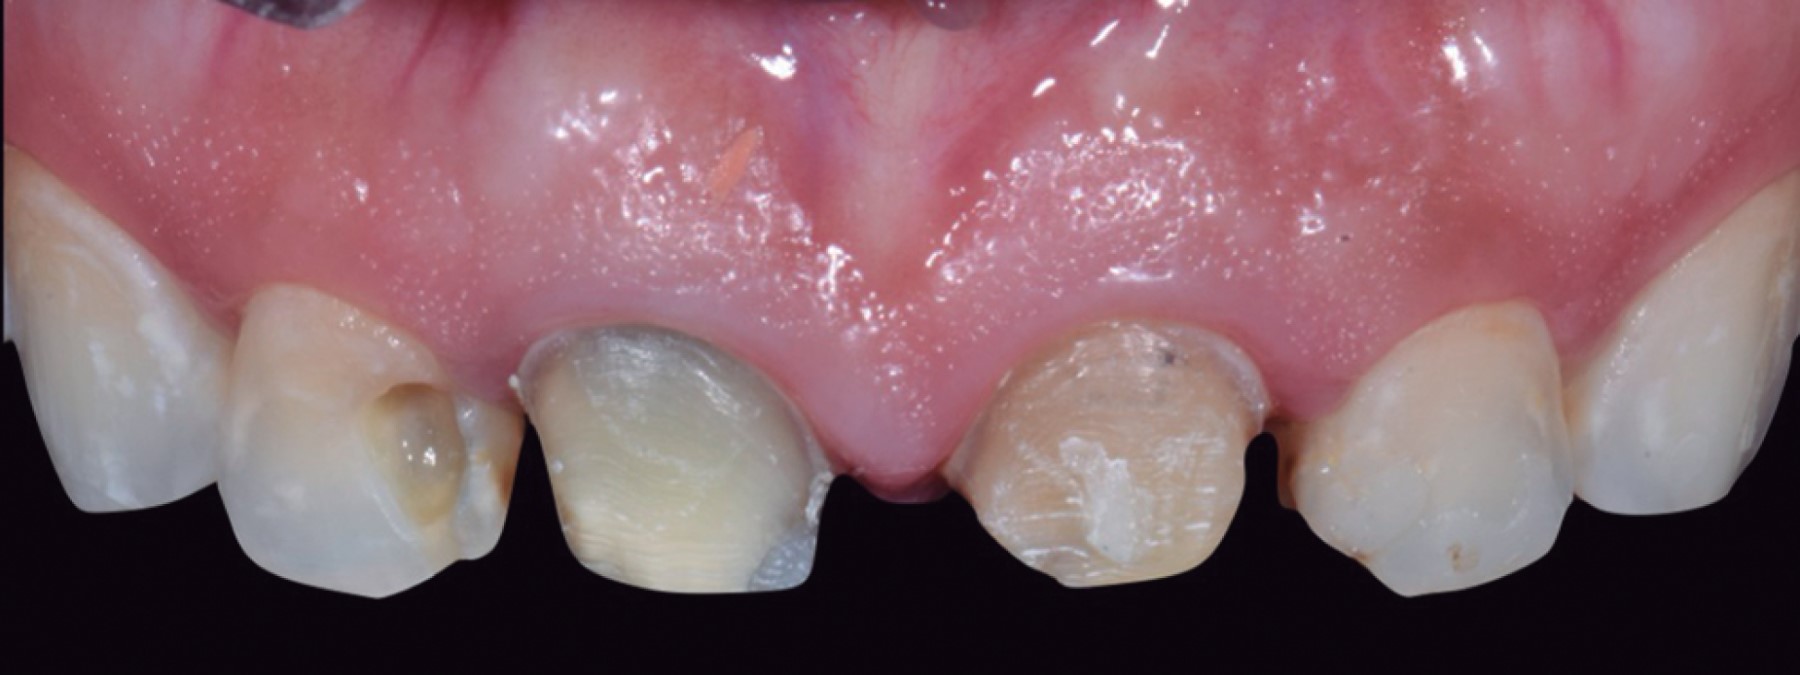

Una vez terminada la fase diagnóstica en donde se evalúan factores estéticos como las formas anatómicas, proporciones dentales, exposición de bordes incisales en reposo y funcionales devolviendo la guía anterior, se retiraron las coronas de los órganos dentarios (OD) 11 y 21, al igual que las lesiones cariosas de los OD 12 y 22 (Figura 4). Se realizó una interconsulta con el departamento de endodoncia y se procedió a realizar tratamiento de conductos a estos dientes. Una vez terminados los tratamientos de conductos se colocaron postes metálicos paralelos (Para-Post) en los OD 11 y 21 debido a que se necesitaba aumentar la altura del muñón protésico para retención de la restauración.10 Una vez sellados los tratamientos de conductos de las cuatro piezas se volvió a colocar el Mock-up para utilizarlo como guía de desgaste para las preparaciones dentales mínimamente invasivas (Figura 5).